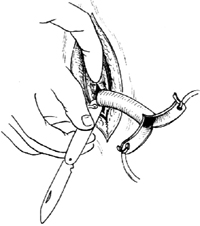

| 2-6 扩开气管切口,插入气管套管 |

| 图2 气管切开术 |

6.插入气管套管 切开气管前壁软骨环后,即用弯止血钳或气管插管扩张器扩开气管切口,随即插入带芯气管套管[图2-6]。如病人有强烈咳嗽,应立即拔出管芯,并用吸引器吸尽气管内分泌物及血性液体,再放入内套管。证实套管已插入气管内后,方可将两侧拉钩取出;如无气体进出,应拔出气管套管。重新放置。